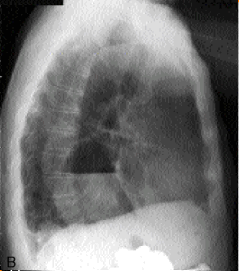

Meme cas :

Cliche profile gauche . Le niveau hydro-aerique

situe au mediastin inferieure et posterieure . |